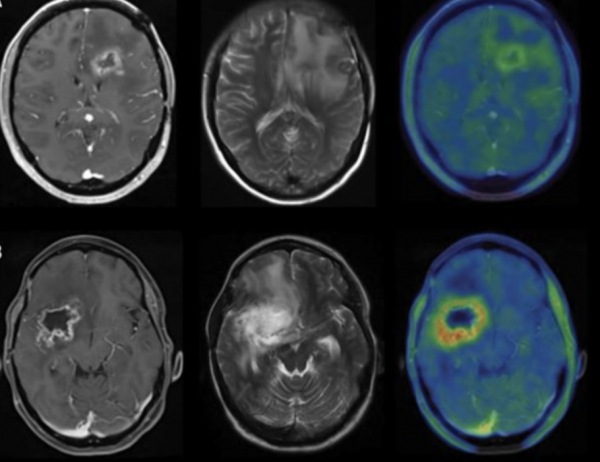

07.09.2025 Zalecenia ESTRO/EANO dotyczące ponownej radioterapii u chorych na glejaka wielopostaciowego.